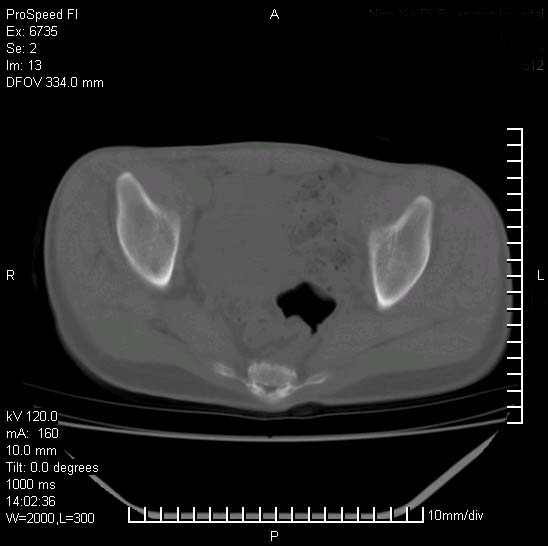

患者自诉胯部疼痛两年余,在当地服用中药,半月前至本院考虑骶髂关节结核,给予抗痨治疗。现发展至右下肢疼痛明显,活动受限,以膝关节处明显,拍膝关节平片无明显异常。

两侧骶骼关节改变,考虑强直性脊炎

左侧骶髂关节面限局性骨破坏,边缘硬化关节腔见钙化物;不出外tb

右侧骶髂关节也有类似改变,只是较左侧轻,首先考虑强直性脊柱炎,不除外结核,建议作hla-b27检查。

典型强脊炎改变,髋关节亦有累及

符合强直性脊柱炎表现。